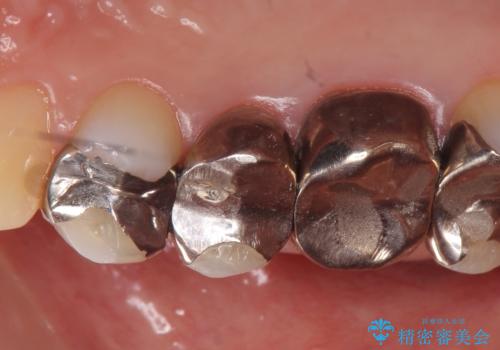

- ものを咬むと右上の歯が痛むといらっしゃった方の症例です。

検査の結果右上5の歯の神経が死んでいたため、根管治療を行った後に、オールセラミッククラウンによる補綴を行いました。

また右上6に関しては再根管治療を行い、右上4に関しては虫歯治療を行った後に、オールセラミッククラウンによる補綴を行いました。